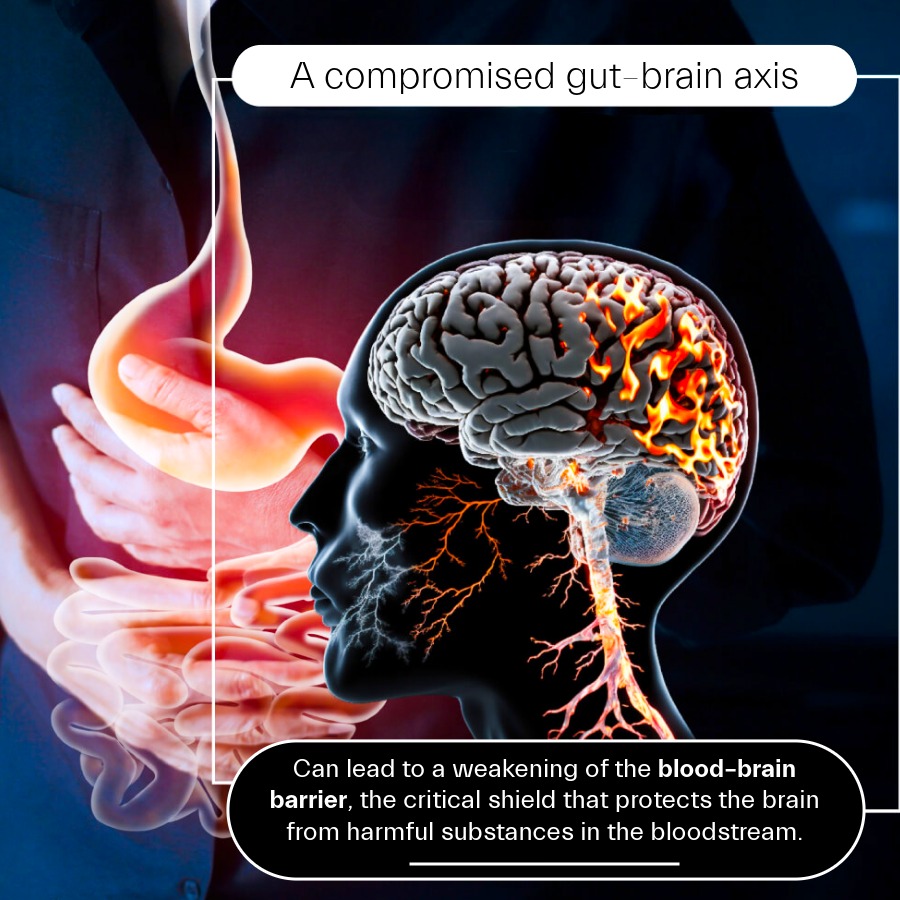

The implications, though, go far beyond food cravings. A compromised gut–brain axis may also weaken the blood–brain barrier, the critical shield that protects the brain from harmful substances in the bloodstream. When this barrier becomes more permeable, it can trigger inflammation in the brain, a process increasingly linked to neurodegenerative conditions such as Alzheimer’s and Parkinson’s disease.

Blood-brain barrier response

Explores the connection between the microbiome and the gut and blood-brain barrier systems, as well as the improved effect that ION* has on the blood-brain barrier.